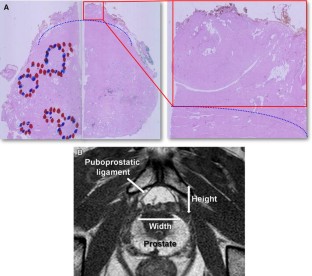

We prospectively collected data that included the results of prostate MRI and continence recovery of patients who underwent RP. From April 2006 through February 2010, 862 patients underwent RP. Of these, a total of 731 cases were included in the final analysis. The height and width of the DVC were measured in the T1-weighted axial image at the level that showed the puboprostatic ligament.

The continence rate of the total patient cohort at 12 months was 96.7 %. The mean width, height and area of the DVC were 2.0 ± 0.4 cm, 1.2 ± 0.3 cm and 1.8 ± 0.6 cm2, respectively, and there was no linear correlation between continence recovery and these parameters. However, the patients who had a moderately large-sized DVC (2.3–2.8 cm2) regained their continence significantly sooner (mean duration = 2.1 months) than those with small (3.7 months, p = 0.002) or extremely large DVC (4.0 months, p = 0.006). In a multivariate analysis, DVC size, age, transfusion and the length of membranous urethra were significant predictors of continence recovery.